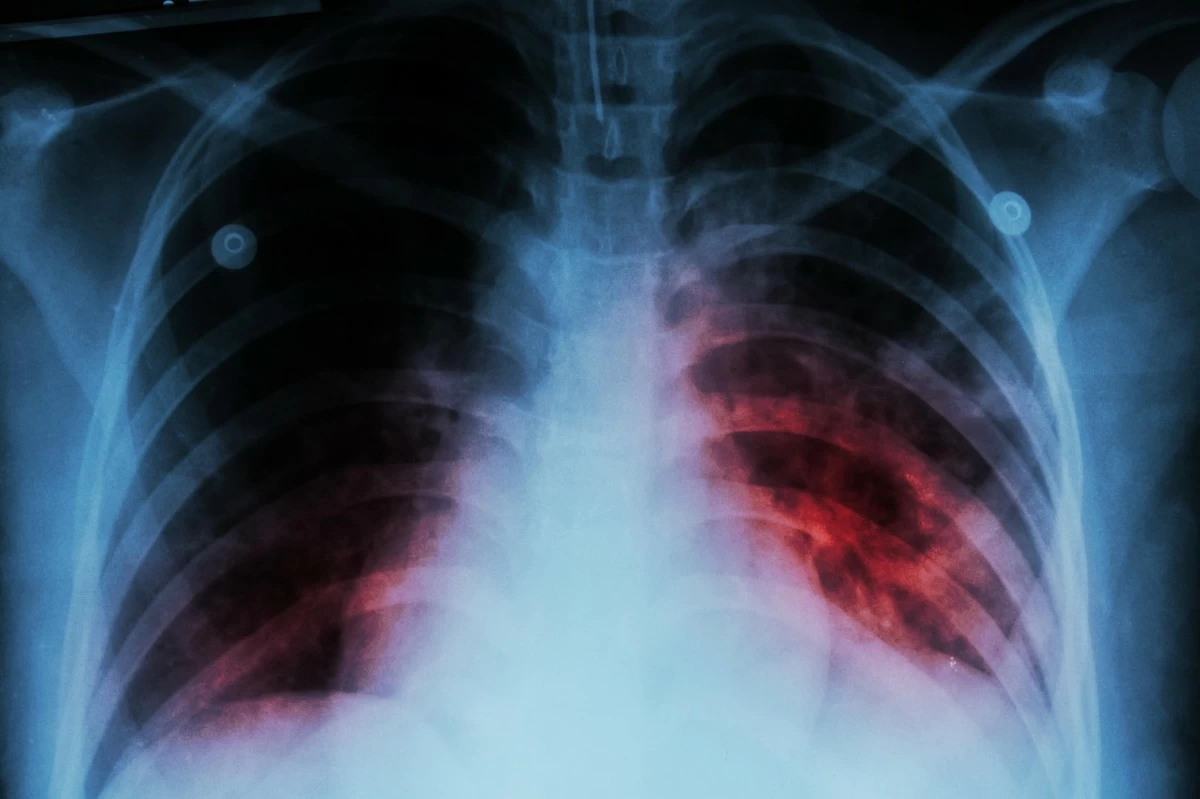

SYDNEY, March 2: Researchers in Australia have discovered how a promising class of experimental antibiotics disrupts the bacterium that causes tuberculosis (TB), raising hopes for improved treatments against drugresistant strains. TB remains one of the world’s deadliest infectious diseases, killing about 1.2 million people every year, with drug-resistant strains posing a growing threat, particularly in the Asia-Pacific region, said a statement from Australia’s Centenary Institute on Friday.